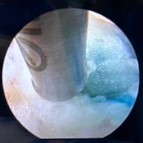

FESS:内視鏡の映像

FESSは、MEDやMELよりもさらに低侵襲な手術で、直径7mmの筒を用いてヘルニアを摘出したり、神経を圧迫する靭帯や骨を切除したりする手術法です。水を流しながら行うため、水圧で出血が抑えられます。また、術野が常に洗浄されている状態になり、感染予防にも効果があるとされています。